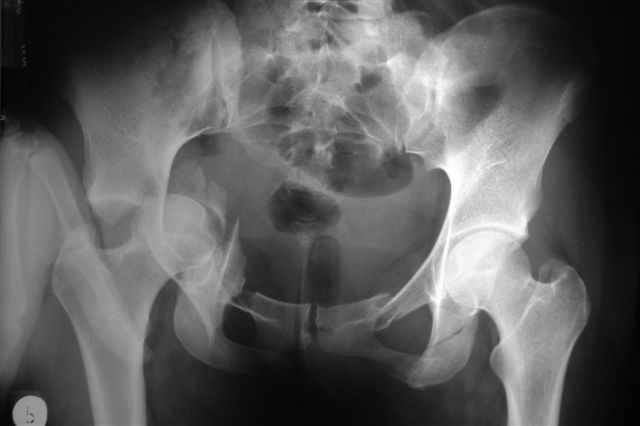

Трудности возникли сразу после рассечения большой ягодичной мыцы - короткие наружные ротаторы едва ли определялись - головка и шейка (как видно на

снимке) ушли в таз, пришлось воспользоваться дистрактором( ручные попытки выдернуть голову из под проксимального фрагмента - безуспешны) Шарнирный дистрактор - великое изобретение, без него репозиция была просто невозможна.

> Трудности возникли сразу после рассечения большой ягодичной мыцы - короткие

> наружные ротаторы едва ли определялись - головка и шейка

> ( как видно на

> снимке) ушли в таз, пришлось воспользоваться дистрактором

P.S. в приложении R пациентки с похожей проблемой доступа.. за исключением того, что перелом

двухколонный. Вертлугу лечили Y доступом.